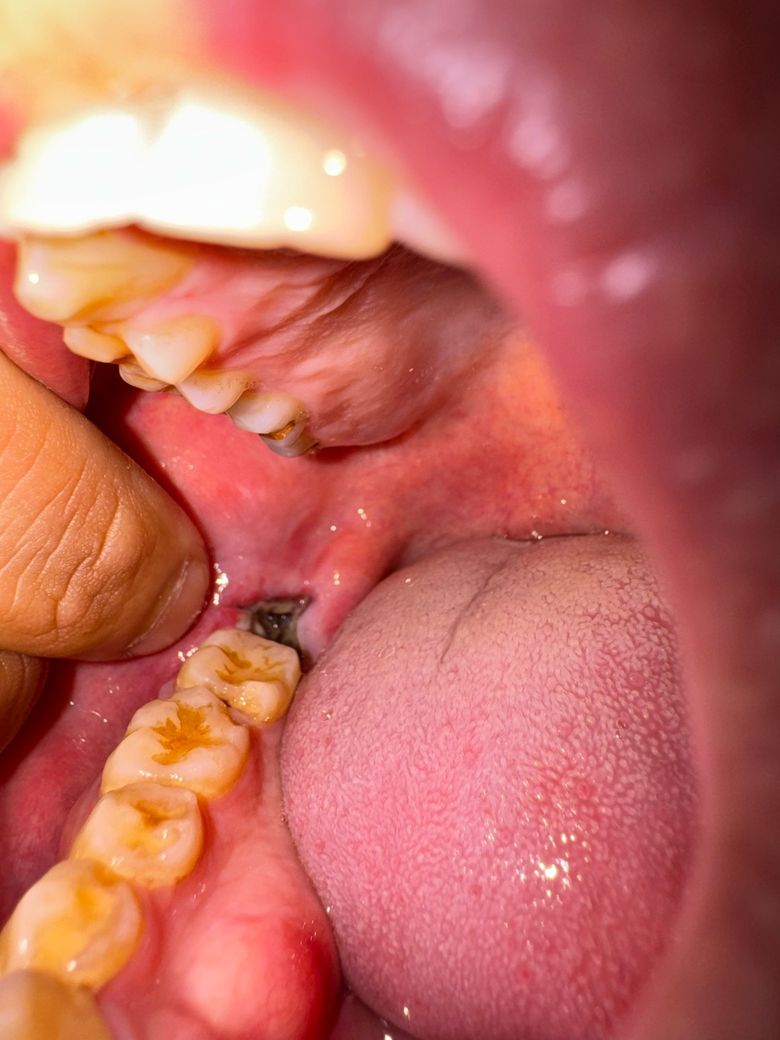

곧 사랑니 발치 5일차, 이건 뭔가요?

아래 사랑니 발치와 옆

볼쪽이 헐기 시작하더니 통증이 턱부분까지

퍼지고 혹시몰라 볼을 잡아서 당겨확인해보니 볼이 헐은것도 헐은거지만 이런게 있는데 혹시 감염이나 그런건가요… 침을 머금은게 이 부위를 지나가면 약간 비린맛 비슷한게 느껴지는데 뭔가 싶어서요… 혹시 치과 내원해야 하는 상황인가요…

• 1번 째 사진

사랑니를 발치하고 나면 발치한 부위에 혈병이 형성되면서 사진처럼 보일 수 있습니다. 크게 문제가 되는 사항은 아니기 때문에 걱정하지 않으셔도 되지만 발치한 부위를 자극하지 않는 것이 좋습니다. 발치한 부위를 자극하게 되면 출혈이 되고 치유가 늦어질 수 있기 때문입니다.

발치 부위 잇몸이 회복되면서 생기는 염증, 육아조직 부산물이라고 보시면 됩니다. 걱정마세요